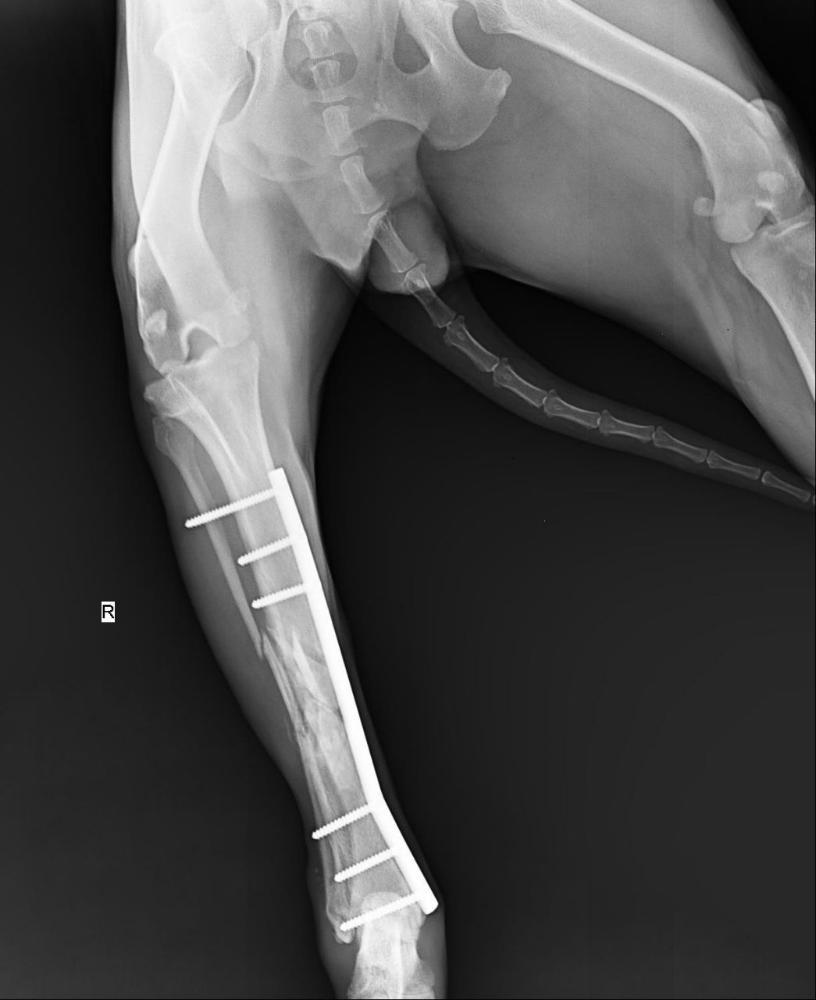

wina Опубликовано 18 января Опубликовано 18 января (изменено) Сдали анализ мочи, расход 900 р, показатели в норме. И- важно- были в клинике Еремина, Док сказал, все хорошо. Лапа собрана на трехмиллиметровой ( в толщину) пластине и 6 штифтах. Док сказал, хорошо, что удалось сохранить длину лапы (!!) , Нора нормально наступает. Остеогенон пить еще месяц хорошо бы. Расход ( рентген) + осмотр 2350. Изменено 18 января пользователем wina 3 4

Светлана 2101 Опубликовано 18 января Опубликовано 18 января Как красиво всё сделано Мастером! Будет бегать девчонка. 3